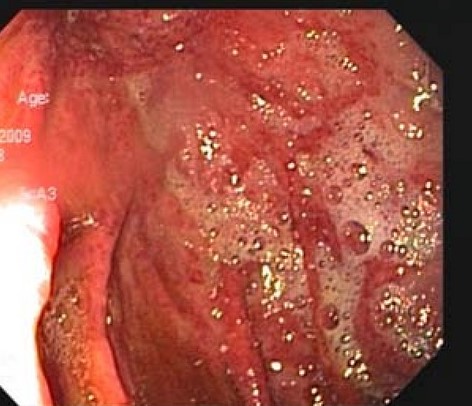

Gastroscopy. Green arrows: orifice of the gastrocolic fistula (Courtesy Dr. V. Penopoulos)